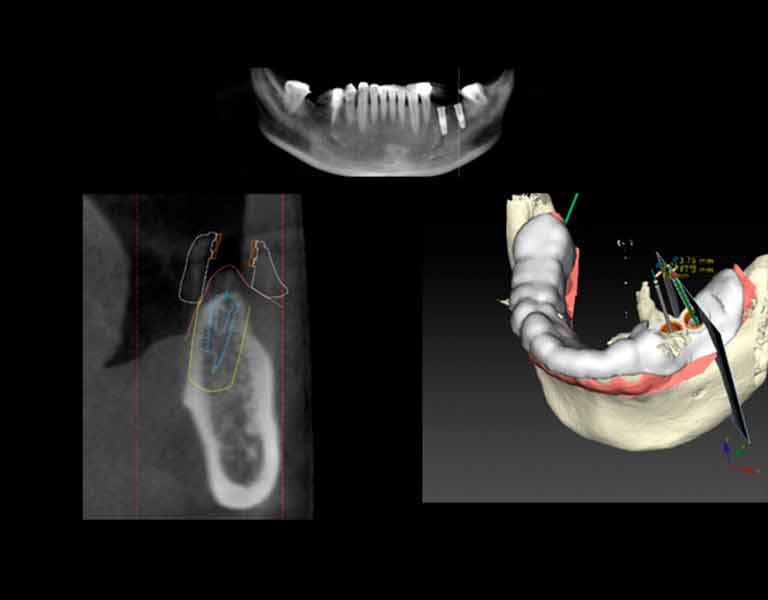

傷口が最小限、スピーディなインプラント手術

フラップレスインプラントとは、従来のインプラント手術とは違って、歯茎を切らずにインプラントを埋め込むことができる技術です。C Tスキャンとコンピュータシミュレーションにより、歯茎を切開せずにインプラント を正確な位置に埋めることができるので、出血や腫れも少なく、早くて安全な手術が可能になります。

歯肉を切らずに手術を行える

ノーベルガイドNobelGuide™システムとは、CTスキャンとコンピュータソフトを使って正確なシミュレーションを行うインプラント手術システムです。従来の治療で必要不可欠だった 切開手術を行わなくても治療が可能なりました。そのため、“より早く・より正確・より安全”なだけでなく、 “より安い”治療が実現したのです。

無駄な手術を回避でき低コスト

インプラント治療での事故は取り返しがつかないこともあります。そんなインプラント治療を担当歯科医の経験と勘だけに任せられますか?例えばタクシーも「ナビゲーションシステム」を装備してより正確でスピーディーなルートを誘導させる時代。インプラント治療にもそんなシステムがあってしかるべきでしょう。インプラント治療のナビゲーションシステムと言えるシステムが「デジタルインプラント」です。